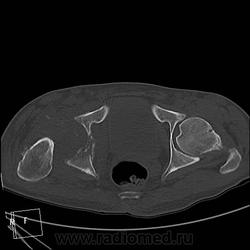

Мужчина 37 лет. Травму отрицает. Верификации нет, и неизвестно, будет ли. Думаю на остеосаркому. Характерно ли такое распространение до L3?

Лежал около месяца в другом ЛПУ, парез, отек конечности, преходящий парез другой конечности, худеет, слабость. К нам однократно в январе привозили на КТ головного мозга для исключения инсульта - исключили. Поступил вчера, в направлении "заболевание спинного мозга?", направлен на КТ грудного и поясничного отдела и таза для исключения мтс в позвоночник и перелом шейки правого бедра. В позвоночнике деструкции не нашла. Анализов пока тоже нет. Температура в норме.

ЗНАЧИТ ТАК - ТУТ ИМЕЕТ МЕСТО ПАТОЛОГИЧЕСКИЙ ПЕРЕЛОМОВЫВИХ В ОБЛАСТИ ПРОКСИМАЛЬНОГО ЭПИМЕТАФИЗА ПРАВОЙ БЕДРЕННОЙ КОСТИ !!САМ ПРОЦЕСС СКОРЕЕ ВСЕГО КАК С ОСТЕОЛИТИЧЕСКИМ ,ТАК И ОСТЕОБЛАСТИЧЕСКИМ КОМПОНЕНТОМ С ПРЕОБЛАДАНИЕМ 1-ГО.ИМЕЕТСЯ МЯГКОТКАННЫЙ КОМПОНЕНТОМ С УЧАСТКАМИ ПОНИЖЕННОЙ ПЛОТНОСТИ и обызвествлениями,разбросанными по периферии!!ПО ПЕРЕДНЕ ЛАТЕРАЛЬНОМУ КОНТУРУ ВЕРХНЕЙ ТРЕТИ ДИАФИЗА И МЕТАФИЗА БЕДРА ОПРЕДЕЛЯЕТСЯ ИГОЛЬЧАТЫЙ ПЕРИОСТИТ. В ПРОЕКЦИИ ЭПИМЕТАФИЗА ОПРЕДЕЛ-СЯ МНОЖЕСТВЕННЫЕ ФРАГМЕНТЫ РАЗНОЙ ДЕНСИМЕТРИЧЕСКОЙ ПЛОТНОСТИ/вдоль повздошных сосудов по задней и паравертебрально определяется инфильтрация восполительная или опухолевая.?местами ограниченные участки с низкой плотностью ,конгломерат увел лимфат -ких узлов ?с включениями извести в проекции крыла повздошной кости и повздшно поясничной мышцы.перелом патологич в области седалищной кости и крыши вертлужной впадины с остеолитическим компонентом ,в теле повздошной кости участок деструкци и со склеротической каймой !!

Почти... не со всем согласна, игольчатого периостита не нашла, но пересмотрю непременно. Переломовывих... ну есть укорочение конечности на 5 см, так ведь от головки бедра ничего не осталось, деструкция и вертлужной впадины, линии перелома как таковой и нет. А нет головки и вертлужки, тогда тоже вывих? Я не придираюсь, я понять хочу. И что в итоге? Как бы вы написали в заключении?

мой диагноз ходросаркома ,которая в отличие от остеосаркомы часто встречается в метаэпифизе бедренной кости+возраст 37лет тоже в пользу 1 ой.на счет перелома он патологический !!!даже если на данный момент нет шейки и головки !просто странно что только сейчас к вам направляют на потдверждение перелома .на счет вывиха даже в случае полного разрушения верхняя треть диафиза не там где нужно,смещена латерально и кзади ,на счет игольчатого периостита ,это конечно мое мнение пересмотрите 5срез в аксиальном костном режиме и 2 во фронтальном .и кстати на пятом в просвете прямой кишки определяется экзофитно растущее образование ? скорее всего это какашка извиняюсь за выражение но все же перепроверте может и то что мне кажется)))))ну и не нравится зона в проекции повздошно поясничной,повздошной и большой поясничной мышц с включениями извести и сниженной денситометрической плотностью ограниченных участков в центре .это может поменять диагноз первичного поражения мышц (саркома ) на кость вторично!предлагаю законтрастировать кишечник и сделать контрастное исследование (болюс)и посмотреть -что за природа этого участка .?